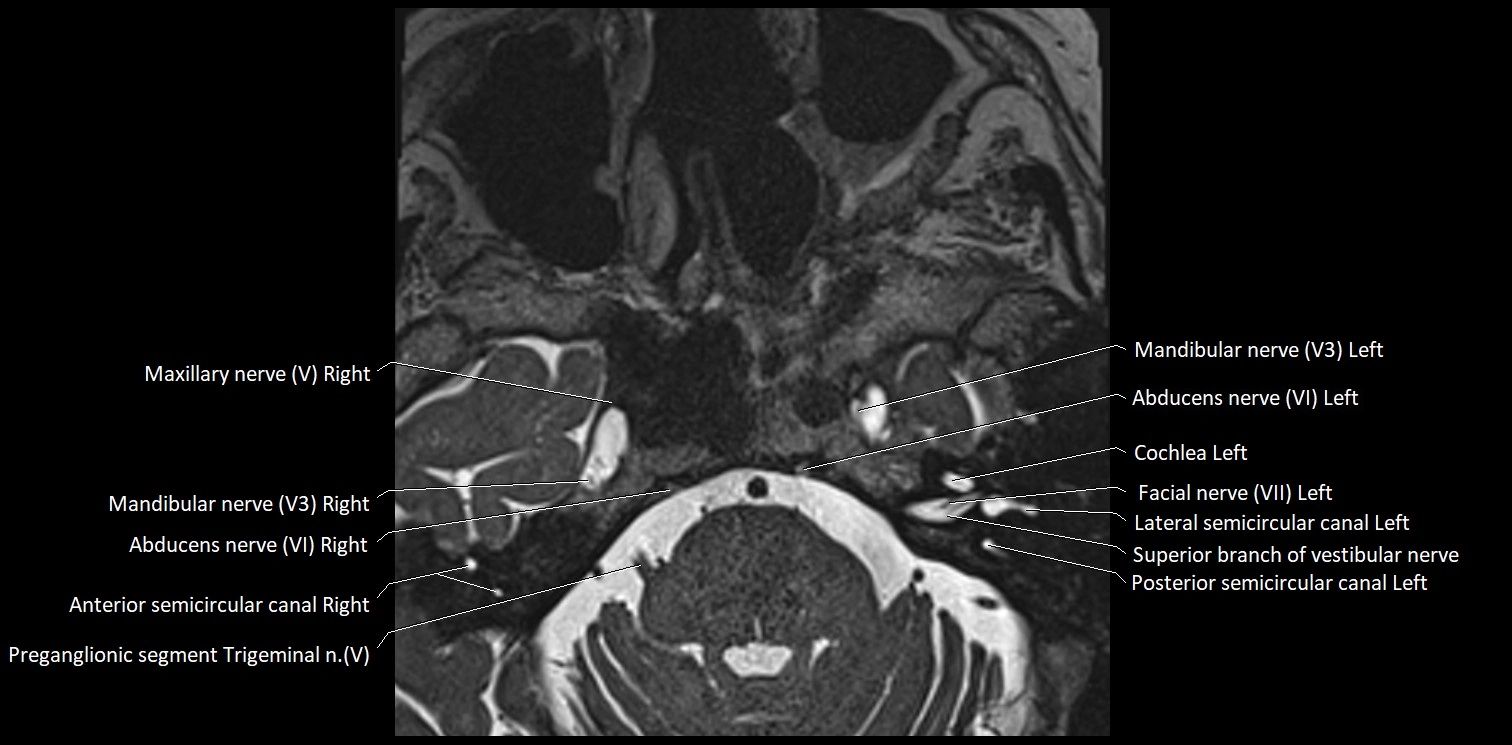

MRI Appearance

• The abducens nerve is a small, thin, linear structure

• Best visualized on high-resolution T2-weighted 3D MRI sequences (e.g., FIESTA or CISS)

• Seen as a hypointense (dark) line running from the brainstem at the pontomedullary junction, traversing the prepontine cistern, and entering Dorello’s canal under the petrosphenoidal ligament, then into the cavernous sinus, and finally the orbit

• May be challenging to visualize in standard MRI due to its small size

• Pathology may be inferred by absence, displacement, or enhancement of the nerve

MRI images

image